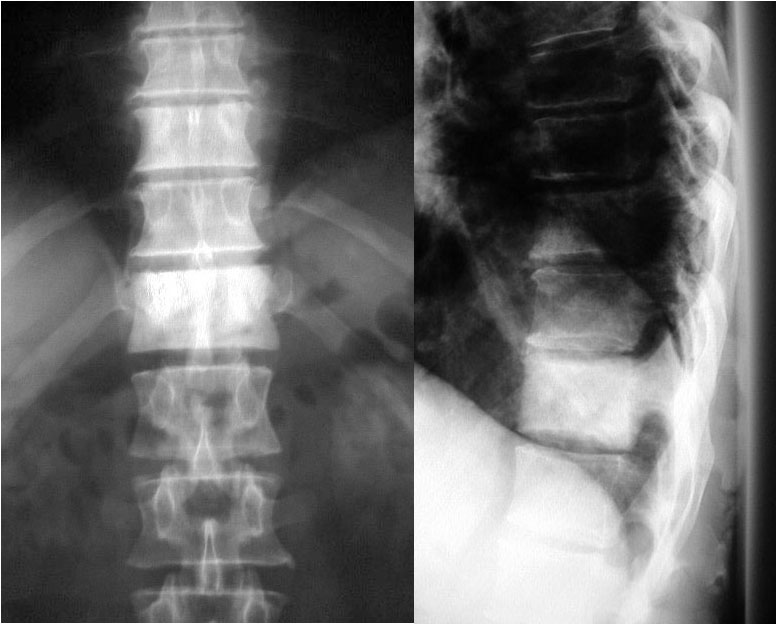

SIGNO DEL SURCO FEMORAL LATERAL

Signo indirecto de rotura del ligamento cruzado anterior (LCA) en la radiografía simple. Se trata de una depresión anormalmente profunda del surco cóndilo-patelar lateral o surco femoral lateral (flecha). Este surco es una pequeña depresión normal en la superficie articular del cóndilo, entre la curvatura que articula con la rótula y la que gira sobre la tibia. El surco anormalmente profundo se produce en la fractura osteocondral impactada, que acontece al tiempo que la rotura del LCA, ya que el mecanismo de ambas lesiones es el mismo: rotación de la articulación y valgo forzado, en el que chocan el platillo tibial contra el cóndilo femoral.

Imágenes de resonancia magnética de la rodilla, que muestran cortes sagitales de una secuencia potenciada en T1. La fotografía de la izquierda muestra como el surco femoral lateral es anormalmente profundo y se acompaña de una disminución de la señal del hueso adyacente por edema medular (flecha blanca). A la derecha, corte en el que debería verse el LCA, ausente por rotura.

Referencias:

Cobby MJ y cols. The deep lateral femoral notch: an indirect sign of a torn anterior cruciate ligament. Radiology 1992; 184: 855-858.

Pao, DG. The lateral femoral notch sign Radiology 2001; 219: 800-801. En:

http://pubs.rsna.org/doi/pdf/10.1148/radiology.219.3.r01jn12800.